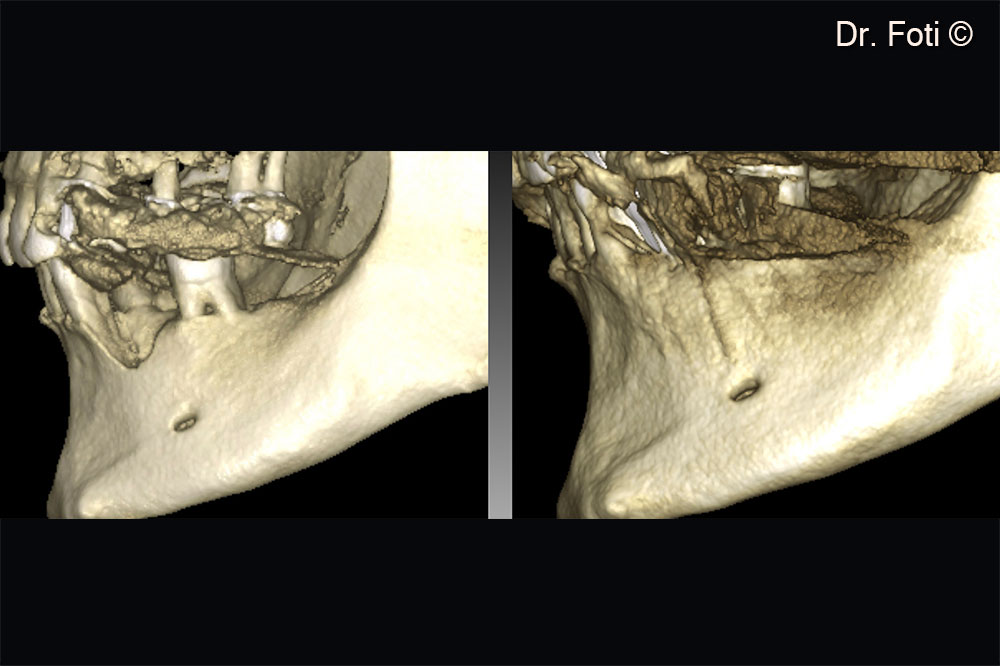

The comparison of the pre-operative and the two-year follow-up. CBCT reveals new bone formation in positions 34 and 35.

The two-year follow-up CBCT shows a vertical bone gain of 6.90 mm